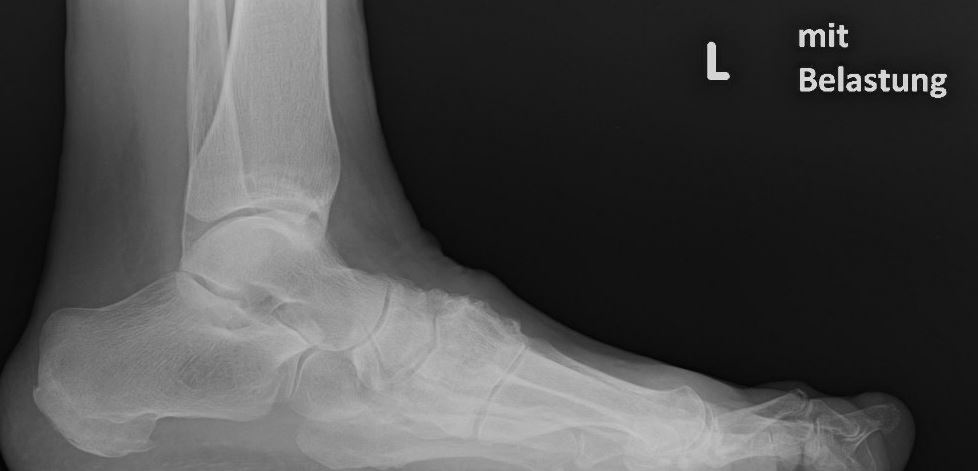

Eine Röntgenaufnahme unter Belastung mit Abbildungen des ganzen Fußes a. p. (mit 15-20° Röhrenkippung) und seitlich, sowie Schrägaufnahmen, reichen meist zur Diagnose. Manchmal ist ein MRT und DVT ergänzend hilfreich. Selten wird die Indikation für ein SPECT CT gestellt (Abb. 6).

• konventionelle Röntgenbilder mit Belastung im Stehen a. p. und seitlich, ggf. schräg (Abb. 9, 10 und 11).